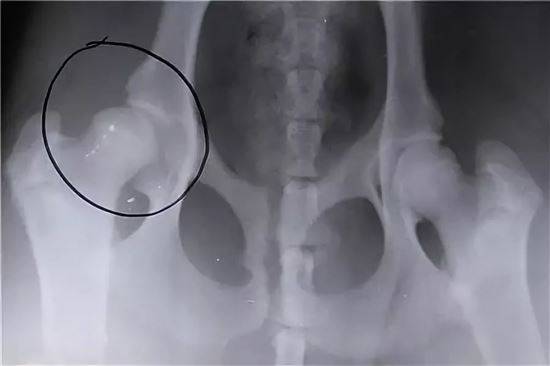

ДИСПЛАЗИЯ ТАЗОБЕДРЕННОГО СУСТАВА У КОШЕК ФОТО